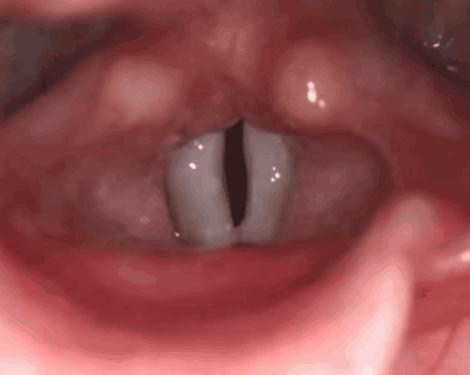

简单的用一句话来概括,声带就是挂在喉咙口的 “门帘”。

图注:喉镜下观察到的声带(从喉咙口往里看)